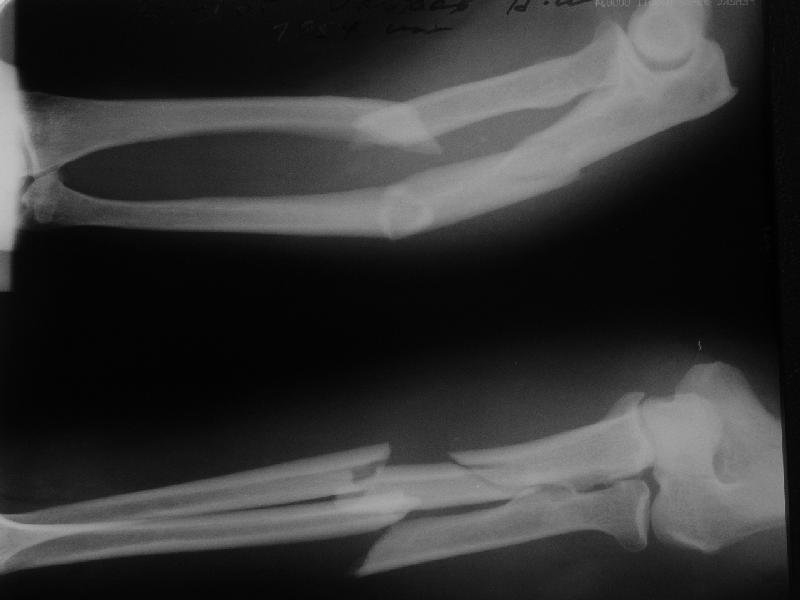

В приложении заключительный момент операции и итоговые снимки. Сделали закрыто. Оба гвоздя (ChM) заперты динамически не только из-за лени ;-) но и

потому, что форма линий излома такова, что и упор будет, и ротационной подвижности на месте переломов не ожидается. Комментарии и критика приветствуются.

The reductions are nice, but I'd be concerned that the fracture of the radius will move with pronation & supination encouraging nonunion (since the nail is essentially fixed to the distal radial shaft and free to move with respect to the proximal radius.

I'd lean toward 4-5 weeks in a long arm cast, giving him "credit" for the past week or so of immobilization.

The reduction is excellent but I am not sure that you have rotational stability of the proximal radial fragment (no proximal locking) this could rotate with pronation and supination. If you are planning to cast then ORIF with plates is superior because casting is not necessary. I would expect these fractures to heal with callus as opposed to primary bone healing seen with plated fixation. Is healing with callus in the forearm a problem? I am not sure I know. How do these rods and locking screws compare price wise with plate and screw fixation (more expensive I would expect)? How often is hardware removal required? What was your operative time? I think these are all factors to consider when comparing a new treatment method with an established one.

Long arm cast for 2 weeks then Active ROM would be my approach. Is the elbow OK ?? radial head looks a little posterior though???

Good technique, but in comminuted / segmental #s like this ,isn't it better to lock statically at both ends? I would be concerned about possible rotation.I dont have any experience with closed nailing of forearm though. Is he going to be in a cast for 6 weeks?

Length 200 and 240 mm, diameter 4 mm.

Yes, the radius. The set includes cannulated reamers 4 and 5 mm. Though finally our custom-made 5 mm hybrid of reamer and awl was used.

Axis, length, radial bowing and rotation are restored. Stability is relative as in any nailing, but enough for early function.